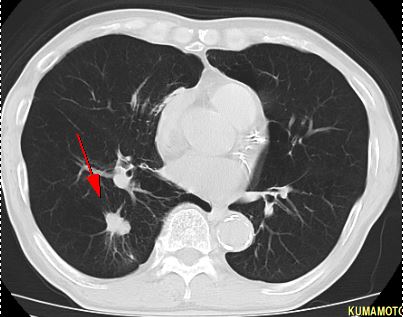

▲早期右乳癌